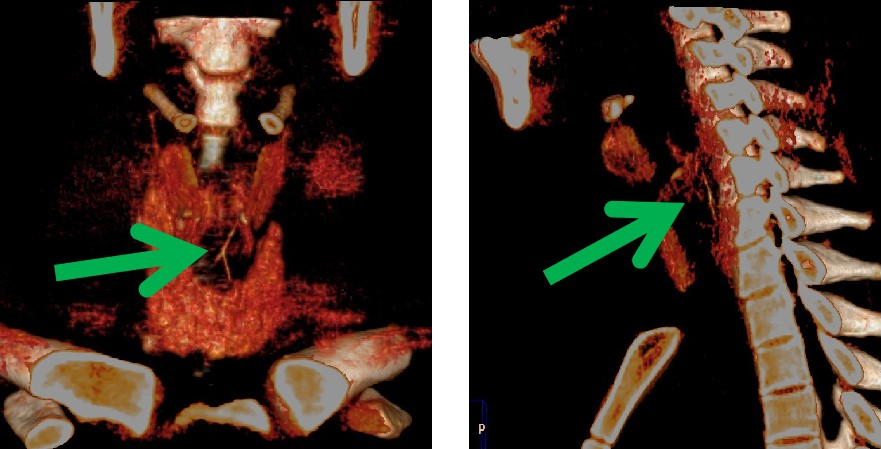

近日,我科来了一位十九岁的患者,一小时前吃鱼,一个不小心,把鱼刺咽下去了。感觉咽部不适异物感,急忙来21点游戏规则 就诊。先进行了喉镜检查 ,没有发现鱼刺的踪影。便连忙来到我科,进行食管异物CT扫描。此时,我科医生的火眼金睛该登场了,果然一下子就发现了罪魁祸首——狡猾的鱼刺。在患者的颈6椎体平面食道内,我们看到一个倒“Y”形的高密度影。我科医生又通过计算机后处理技术,很快这根鱼刺既直观又立体的展现在我们的眼前,鱼刺你终于藏不住了吧!

CT薄层重建图像结合后处理技术能多平面、多方位观察及定位,了解异物与食管壁、周围组织间的关系与损伤程度,主要重建方法包括多平面重建 (multiplanar reconstruction,MPR)、最大密度投影 (maximum intensity projection,MIP) 及容积再现 (volume rendering,VR)。

MPR、VR 及 MIP 多种重建方式的联合应用可对食管异物及早诊断,确定异物大小、形态、走向及位置,能多角度、任意方位地对组织器官进行观察和分析,直观、立体显示异物与周围组织结构的关系及有无并发症,为临床治疗方案的选择提供较大的指导意义,是诊断食管异物的可靠方法,已经成为食管异物诊断的首选检查方法。